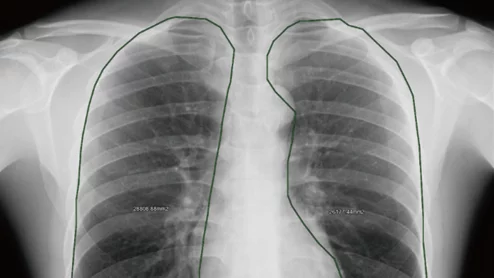

Dynamic chest radiography could be an alternative to pulmonary function tests for diagnosing COPD

The X-ray technique uses continuous radiographic acquisition during respiration to assess lung function.